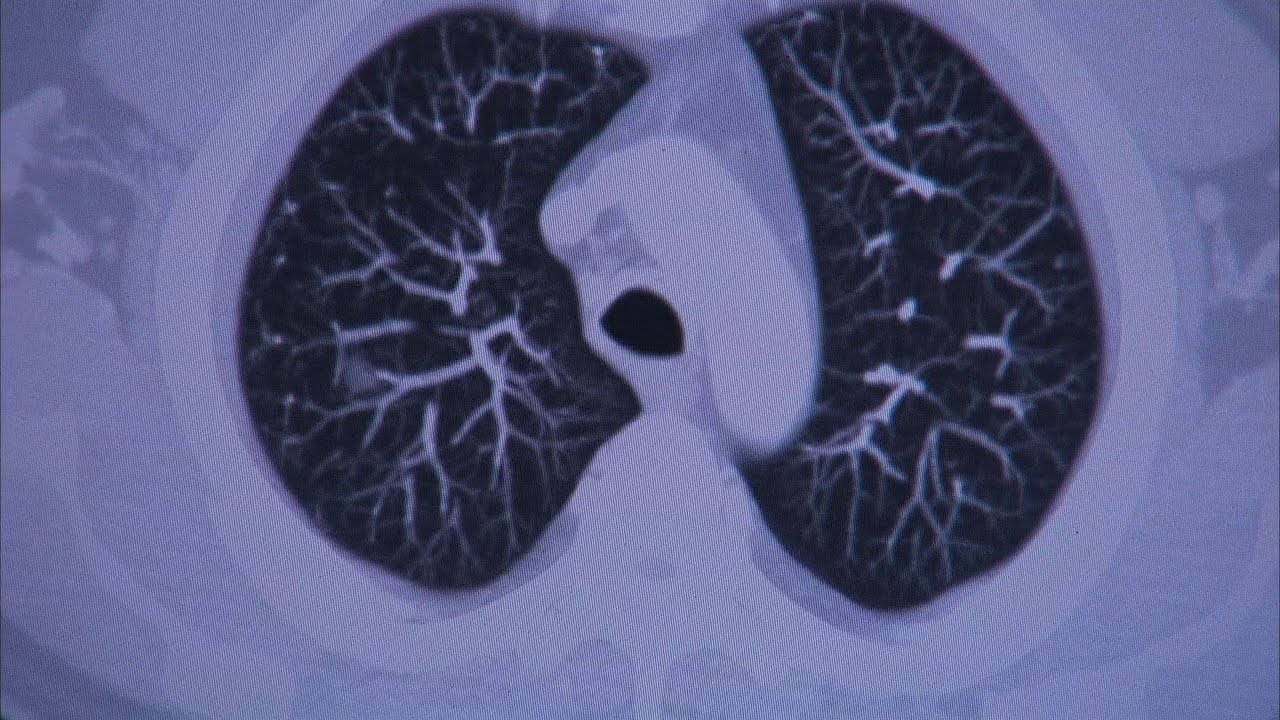

Robotic Bronchoscopy - Mayo Clinic

Описание: Robotic GPS system for early lung cancer detection.